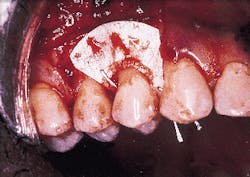

A nonresorbable membrane for GTR was placed over the defect as seen in Photograph #4. The membrane was composed of e-PTFE and was obtained from the W.L. Gore Co. in Flagstaff, Ariz.

Photograph #4: An expanded polytetrafluorethlyne membrane was placed over the root surface and secured. The facial flap was then sutured over the membrane.